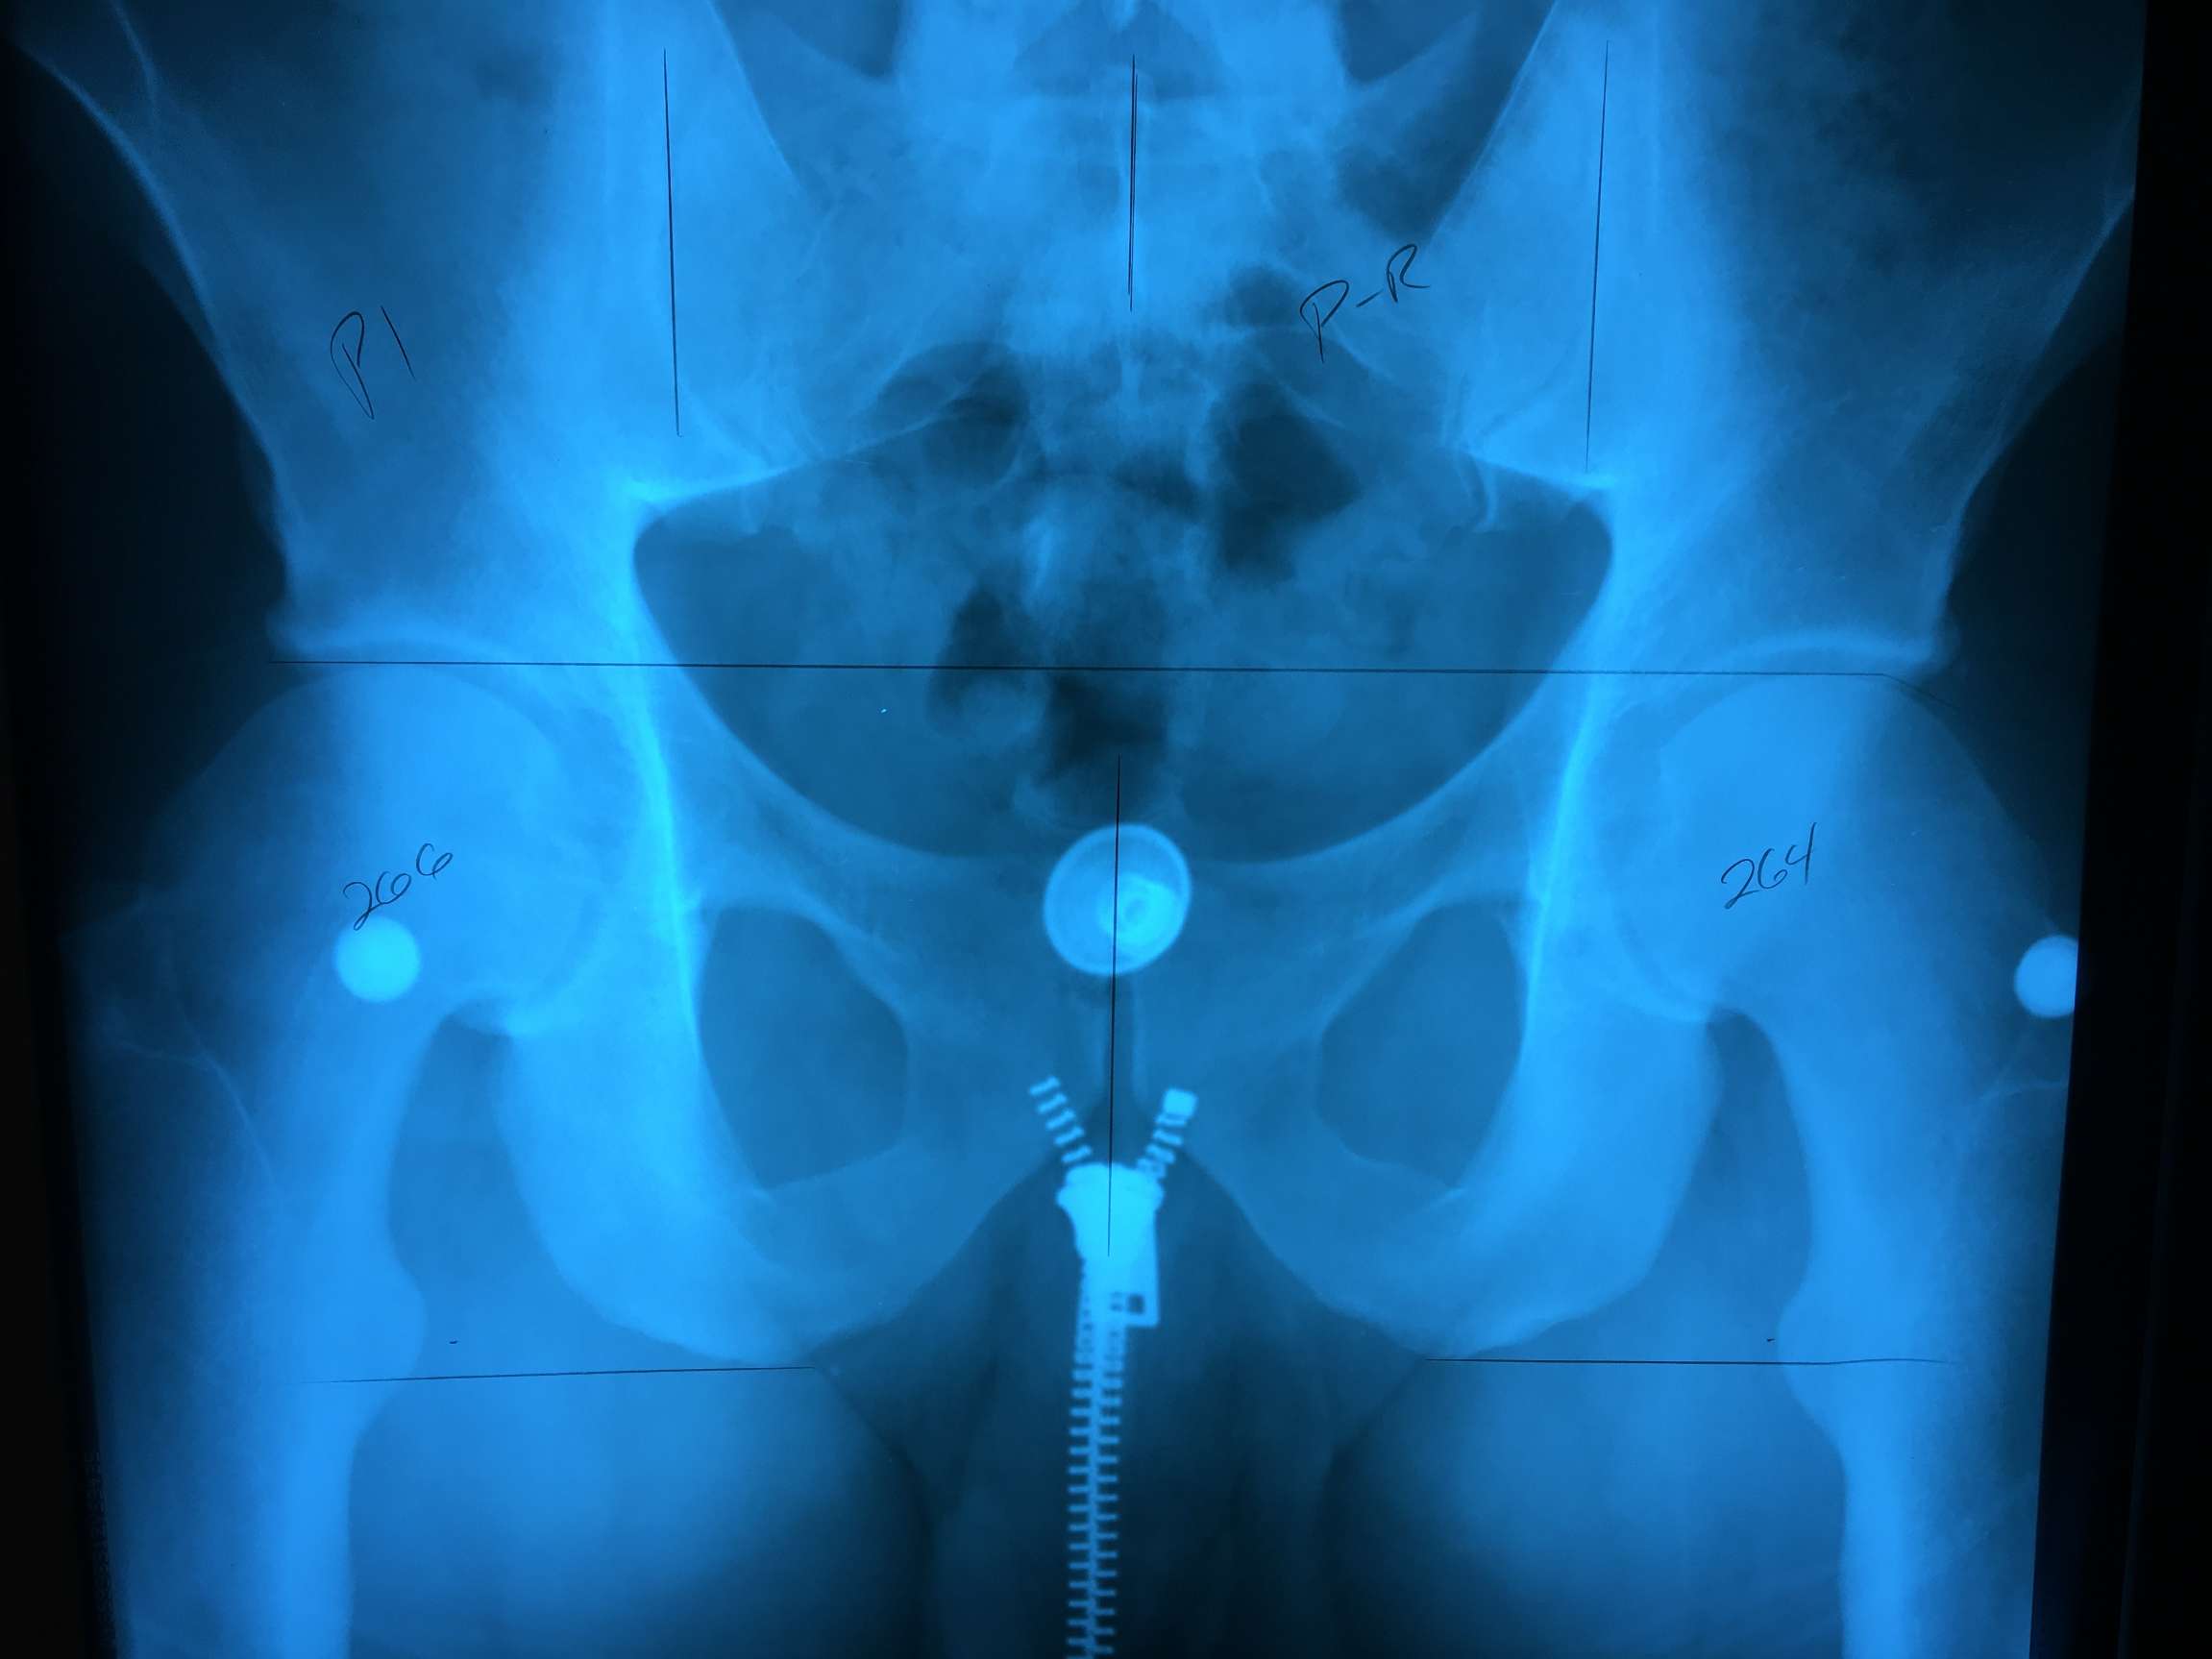

For anyone who hasn’t read this post for a week, here is a little perspective for everyone on the degeneration in my left hip. This first x Ray was taken 6/6/11 when I was 31 years old, still in the prime of my competition days. The second x Ray is from a week ago when my Ortho informed me I had the worst case of Osteo arthritis he’s ever seen in a 39 year old (8 years folks)… it’s amazing how fast things can change, and one of the biggest changes here, is not only the lack of soft tissue between the head of my left femur and the acetabellum, but also the head of my left femur itself… kinda crazy

Wow now I can really see the difference. I noticed that your hip had the white ring with the other image it really shows.

It actually looks like your whole pelvis is crooked? Is it?

I believe that’s from the way the x Ray tech had me stand last Thursday. She shifted all my weight to the left and made me stand in the most excruciatingly painful and awkward position ever. I think it was to pronounce that left side even more